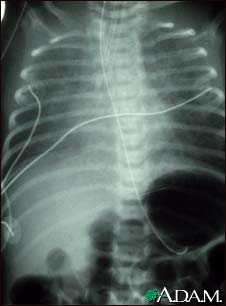

Totally anomalous pulmonary venous return, X-ray

Totally anomalous pulmonary venous return (TAPVR) is a form of congenital heart disease. This x-ray shows an enlarged heart, a large liver, and increased pulmonary vascularity.